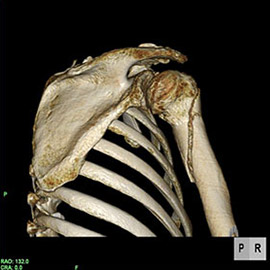

80列マルチスライスCT 検査 画像例

80列マルチスライスCTで撮影した画像

整形